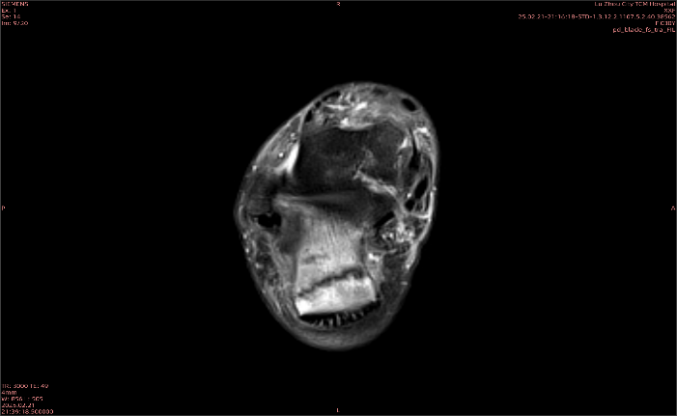

隱性骨折在MRI表現(xiàn)為T(mén)1WI序列上見(jiàn)由關(guān)節(jié)面向骨干走行的形態(tài)各異低信號(hào)區(qū),有線狀、條狀、紊亂低信號(hào),信號(hào)強(qiáng)度不均勻。與T1WI低信號(hào)改變相對(duì)應(yīng)部位在T2WI上表現(xiàn)為相應(yīng)形狀的高、低混雜信號(hào),且部分低信號(hào)周?chē)梢?jiàn)高信號(hào)水腫改變。STIR序列圖像上病灶呈顯著高信號(hào),與信號(hào)被抑制的臨近正常骨髓形成鮮明對(duì)比,分界也較T2WI成像更為清楚。脂肪組織抑制技術(shù)是MRI的一個(gè)重要性能,脂肪抑制技術(shù)在MRI應(yīng)用中可以改善組織對(duì)比和增加病變顯示機(jī)會(huì),這樣骨髓的脂肪抑制后就不會(huì)有任何信號(hào),而隱性骨折線及骨髓水腫的異常高信號(hào)就會(huì)更加明顯的顯示出來(lái)。

舉例圖像

圖1

專業(yè)解釋看不懂沒(méi)關(guān)系,大家看圖1和圖2就可以了,這是同一個(gè)患者跟骨的磁共振和CT圖像,圖1的紅色箭頭指示的黑線就是磁共振圖像顯示的骨折線,一目了然。而對(duì)比圖2的CT圖像上并未顯示異常。

這下大家明白了吧,如果懷疑隱匿性骨折優(yōu)先選擇磁共振檢查